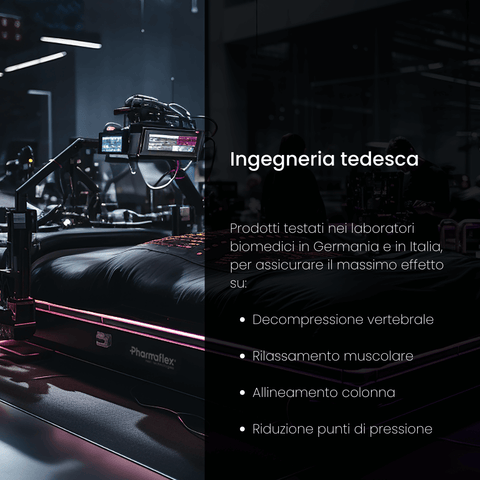

Questa procedura misura come il peso del corpo viene distribuito sulla superficie di riposo. Durante l'analisi, un individuo si sdraia sul prodotto, e con l'ausilio di tecnologie avanzate si rilevano le zone dove il corpo esercita maggior pressione. Questo permette di identificare aree a rischio di stress o disagio, come le spalle, i fianchi o la zona lombare.

Attraverso strumenti all'avanguardia ci impegniamo a monitorare il corretto allineamento del rachide cervicale in ogni posizione di riposo. Lo scopo è di assicurarci che non si verifichino condizioni che possano portare ad uno scompenso muscolare o scheletrico.

Questo test avanzato ad alta precisione ha lo scopo di monitorare la colonna vertebrale prima e dopo l'utilizzo dei nostri prodotti. Confrontando i risultati rispetto ad altri prodotti, i nostri ingegneri biomedici possono valutare con precisione quanto efficacemente l'azione dei dispositivi abbia alleviato la compressione sui dischi e le vertebre.

In questa fase elettrodi sottili vengono attaccati alla pelle o inseriti nei muscoli per registrare i segnali elettrici generati durante le contrazioni muscolari. Questo test è particolarmente importante in quanto ci consente di rilevare l'effettiva capacità di nostri prodotti di ridurre la tensione muscolare e valutare la qualità del riposo.